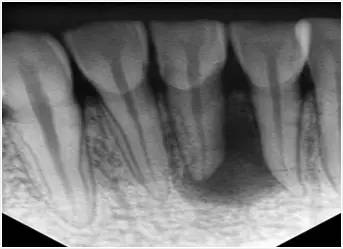

1、術(shù)前拍攝X線片

在根管治療過程中,在根管治療術(shù)前拍X線片,以幫助診斷,了解髓室的位置和根管數(shù)目及形態(tài),測量根管工作長度及日后隨訪和評價療效提供對比的依據(jù)。

X線片顯示根管充填完好,行暫時或永久牙體修復(fù),帶上牙冠,保護(hù)患牙。至此根管治療才可算完成,同時根管治療后還需復(fù)診,一般周期可為3個月、半年、1年、2年或更長。

X片:牙周膜間隙正常或輕度增厚,原有根尖病變縮小或消失;根尖未發(fā)育完全者,術(shù)后3—6個月逐漸形成;根管三維充填,根充物距根尖0.5—2.0mm。